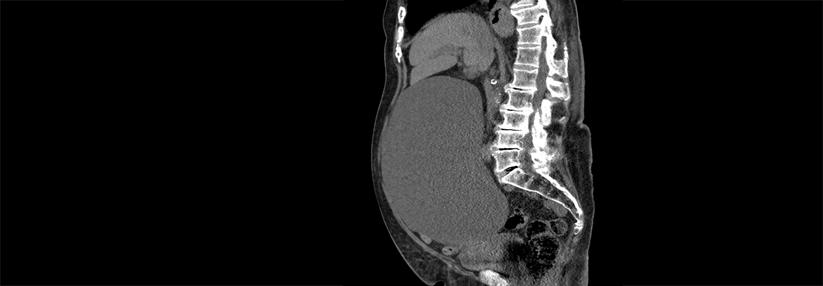

Dieser Frage gingen Kollegen um Aafke H. van Dijk von der chirurgischen Abteilung am Amsterdam University Medical Center nach. Sie nahmen 1067 Patienten mit Abdominalschmerzen und sonographisch nachgewiesenen Gallensteinen in eine randomisierte Multicenterstudie auf. Die…